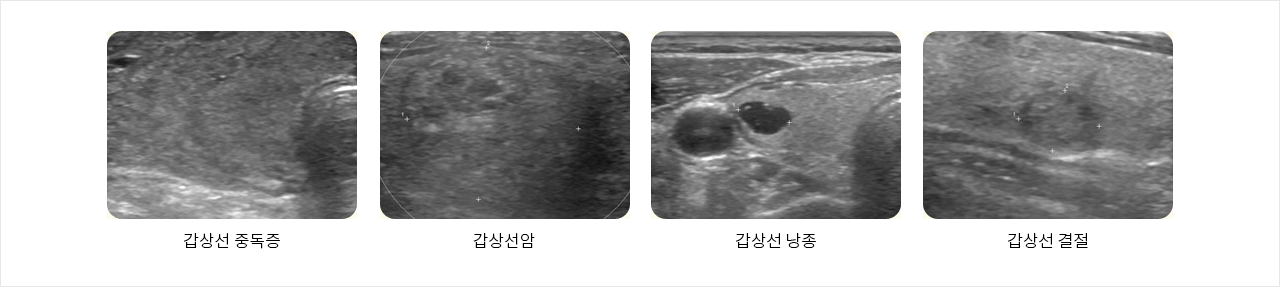

갑상선 초음파는 갑상선의 모양, 크기, 결절의 성상을 관찰하는데 이용됩니다. 인체에 전혀 무해한 초음파를 몸 안에 투과시켜 나타나는 영상을 모니터로 관찰하여 갑상선의 이상 유무를 알아내는 검사로 방사선을 사용하지 않으므로 안전하고 반복하여 검사해도 고통이 없는 검사법입니다.

특히 갑상선 결절이 있는 경우 결절의 내용물이 고형인지 낭종인지 판별이 가능하며, 치료 후 결절의 크기 변화를 추적 관찰하는데 유용합니다. 최근에는 갑상선 질환이 증가하여 현재 우리나라 암 순위 5위를 차지하고 있습니다.

갑상선의 기능은 혈액검사를 통해 알 수 있지만 갑상선 검진을 정확하게 하기 위해서는 실제로 종양을 판별할 수 있는 갑상선 초음파와 혈액검사를 함께 병행해야 합니다.

- 갑상선 중독증

- 갑상선암

- 갑상선 낭종

- 갑상선 결절